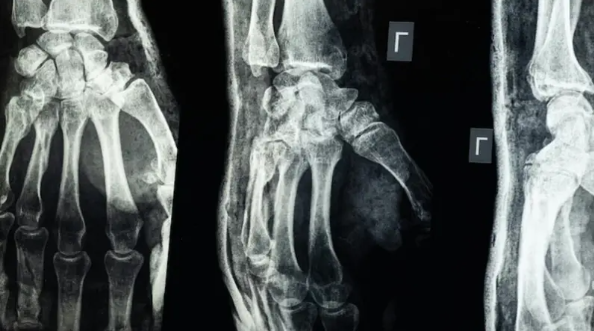

لا داعي لزراعة المسامير والصفائح .. “غراء طبي” يجبر العظام المكسورة في “3 دقائق” فقط